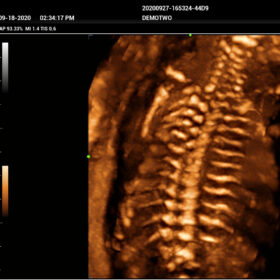

- Smart Scene 3D – Full Stack smartness obstetric solution empowered by ZST+. Comprehensive 3D/4D OB imaging solution with comprehensive fetal parts coverage.